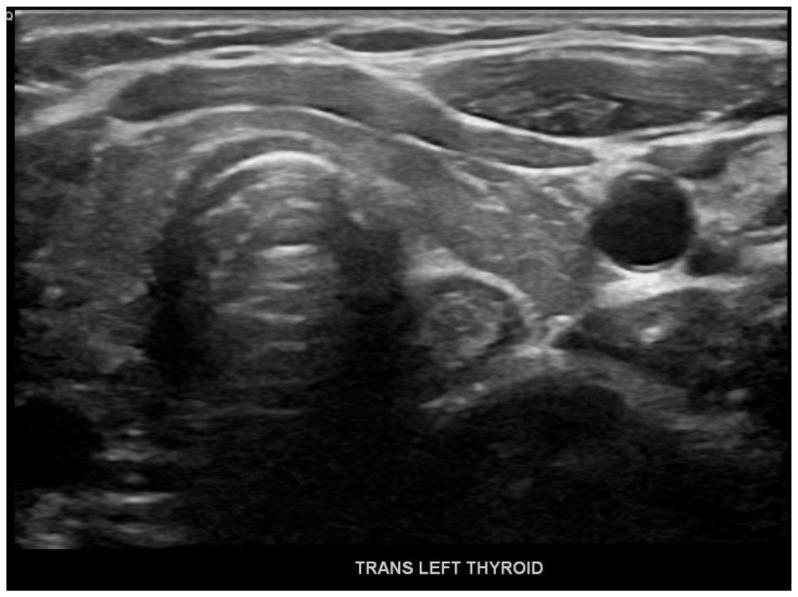

Immune Checkpoint inhibitors (ICIs) such as nivolumab, pembrolizumab, and ipilimumab are monoclonal antibodies against cytotoxic T lymphocyte antigen 4 (CTLA4) or program death (PD)1 and its ligand PDL1. Agents targeting PD1, such as pembrolizumab, have shown widespread efficacy in the past and are also associated with a wide range of immune-related adverse events (irAEs), including endocrine toxicities. A 31-year-old female with a medical history significant for Stage IIb Breast cancer on chemo and immunotherapy (pembrolizumab) presented with nausea, vomiting, and generalized abdominal pain. Laboratory studies showed a blood glucose level of 356 mg/dl, elevated Anion gap 18 meq/L, beta-hydroxybutyrate 46 mg/d, and low C-peptide levels <0.10 ng/ml. The patient was treated for Diabetic Ketoacidosis (DKA). Further testing revealed high Thyroid Stimulating Hormone (TSH) levels along with elevated thyroid peroxidase levels of 38 IU/L. After discharge from the hospital on insulin and levothyroxine therapy, the patient reported increasing fatigue and further testing revealed low cortisol levels <0.5 mcg/dl with elevated ACTH consistent with primary adrenal insufficiency. The patient was started on hydrocortisone therapy with improvement in symptoms. Endocrine toxicities are not uncommon in patients receiving pembrolizumab, but polyendocrinopathy in a relatively rare side effect of pembrolizumab. Only a few cases of pembrolizumab-induced polyendocrinopathy have been reported so far which we have mentioned in this article. While patients are on immunotherapy, close monitoring for clinical signs & symptoms can lead to an early diagnosis, substantially improving morbidity and mortality.

免疫检查点抑制剂(ICIs),如纳武单抗、帕博利珠单抗和伊匹木单抗,是针对细胞毒性T淋巴细胞抗原4(CTLA4)或程序性死亡(PD)1及其配体PDL1的单克隆抗体。靶向PD1的药物,如帕博利珠单抗,过去已显示出广泛的疗效,并且还与多种免疫相关不良事件(irAEs)相关,包括内分泌毒性。一名31岁女性,有IIb期乳腺癌病史,正在接受化疗和免疫治疗(帕博利珠单抗),出现恶心、呕吐和全腹痛。实验室检查显示血糖水平为356mg/dl,阴离子间隙升高至18meq/L,β-羟丁酸为46mg/d,C肽水平低<0.10ng/ml。该患者接受了糖尿病酮症酸中毒(DKA)治疗。进一步检查发现促甲状腺激素(TSH)水平升高,同时甲状腺过氧化物酶水平升高至38IU/L。出院后接受胰岛素和左甲状腺素治疗,患者报告疲劳加剧,进一步检查发现皮质醇水平低<0.5mcg/dl,促肾上腺皮质激素(ACTH)升高,符合原发性肾上腺功能不全。患者开始接受氢化可的松治疗,症状有所改善。内分泌毒性在接受帕博利珠单抗治疗的患者中并不罕见,但多内分泌病是帕博利珠单抗相对罕见的副作用。迄今为止,仅报道了少数几例帕博利珠单抗诱导的多内分泌病病例,我们在本文中已提及。当患者接受免疫治疗时,密切监测临床体征和症状可实现早期诊断,大幅提高发病率和死亡率。